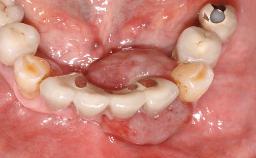

A 77-year-old male patient was referred for the management of frequent and repeated acrylic fracture of his existing mandibular fixed full-arch implant-supported metal/acrylic prosthesis. He also complained about softtissue soreness and the lack of retention and stability of his maxillary removable partial metal/acrylic prosthesis. Both prostheses had been delivered two years previously as part of his full-mouth rehabilitation (caries, tooth wear, tooth fracture). His medical history revealed high blood pressure, controlled with the use of antihypertensive medication.